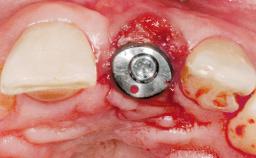

| Type of Implants | One-Piece|Reduced-Diameter |

| Attachment | One-Piece|Reduced-Diameter |

| Placement Protocol | Immediate implant placement |

| Socket Morphology | Single-root socket |

| Socket Integrity | Sufficient, with intact bone walls |

| Bone Volume | Sufficient, with intact walls |